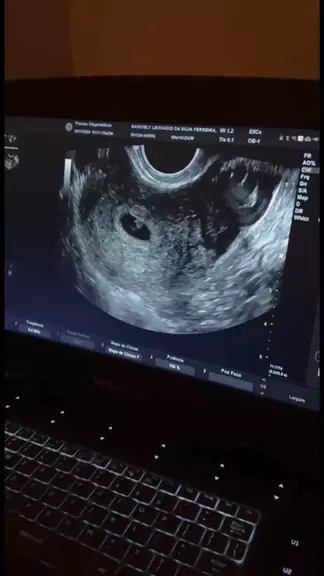

Primeira ultrassom